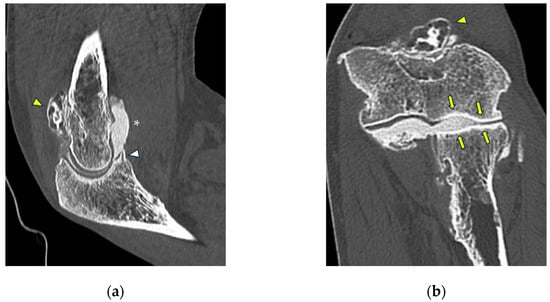

Figure 6.

CT-arthrography of a professional motocross rider with chronic elbow pain due to repeated microtraumatism. (a,b) Axial and sagittal images show pathological widening of the postero-lateral recess (yellow arrows); (b,c) sagittal and coronal images show articular asymmetry of the humero-radial joint (asterisks), diffuse cartilage fraying and a full-thickness chondral defect (grade IV) of the posterior aspect of the radial head dish (yellow arrowhead).

Figure 7.

CT arthrography of a patient with overuse-related lateral elbow pain. (a) Sagittal image shows pathological widening of the radio-humeral and radio-annular recesses (white arrowheads) due to ligamentous laxity—in particular, the annular ligament (white arrow) is displaced distally to the proximal half of the radial head side, which also shows anterior cartilage thinning and synovial thickening (asterisk); (b) the corresponding coronal reformat may aid in precise localization of the proximal extremity of the annular ligament, which can be visualized as a hypodense band anterior to the radial head (white arrows); in this instance, it shows marked distal displacement.